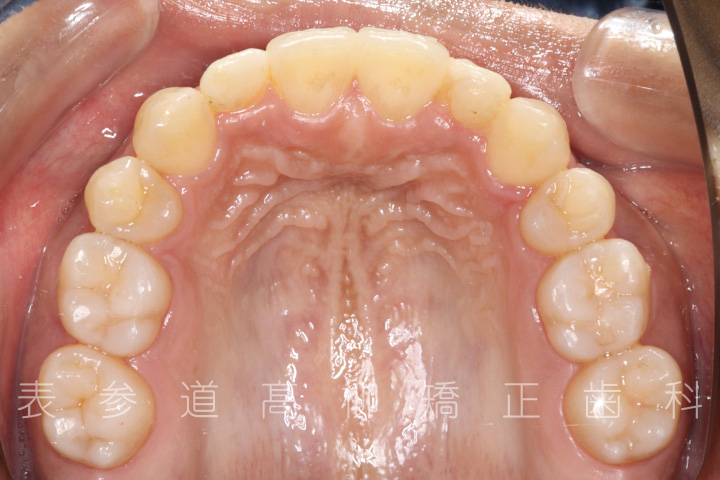

・2⏊2矮小歯(先天的に形態が小さい歯)

・上顎左側第一小臼歯、右側第二小臼歯を抜歯

・矯正治療終了後 加部歯科医院(https://kabe-dent.net) にて2⏊2補綴処置を行った

術前術後の比較